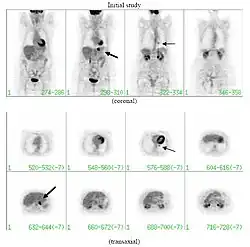

При среднем риске злокачественности, по возможности, проводится плановое ПЭТ-исследование (позитронно-эмиссионная томография). Приблизительно у 95 % пациентов со злокачественным новообразованием в лёгком ПЭТ-картина обнаруживает патологические изменения в лёгочной ткани; у 78 % пациентов с доброкачественным новообразованием ПЭТ-картина патологию не обнаруживает[7]. Таким образом, позитронно-эмиссионная томография надёжно выявляет злокачественные новообразования в лёгких, однако в ряде иных случаев (например, при воспалении, инфекционном процессе) патологический очаг также выявляется. При диаметре образования менее 1 см проведение ПЭТ не целесообразно в связи с повышенной возможностью ложно-отрицательного результата[7][8][9]. Злокачественные новообразования обычно имеют высокий метаболизм, что проявляется при ПЭТ высоким потреблением фтордезоксиглюкозы (ФДГ).

Помимо КТ и ПЭТ, для оценки солитарных лёгочных узлов применяются ПЭТ-КТ (одновременное ПЭТ и КТ-сканирование с наложением полученных изображений), МРТ или однофотонная эмиссионная компьютерная томография (ОФЭКТ)[11] .